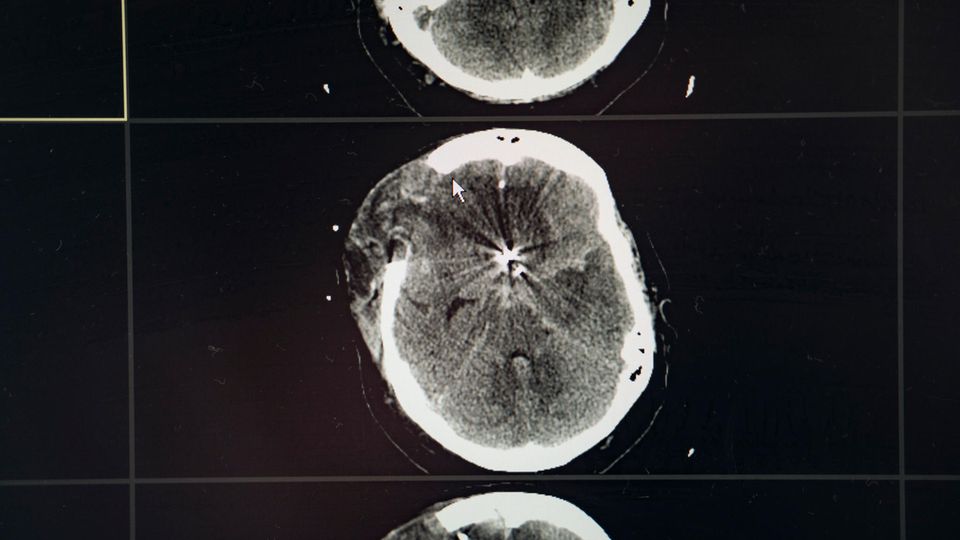

Er führt uns in ein Zimmer, in dem eine Frau liegt. Sie ist um die 50 Jahre alt. Hat dunkles, langes Haar. Ihre rechte Kopfhälfte ist stark angeschwollen. Die Beatmungsmaschine pumpt in regelmäßigen Stößen Luft in ihre Lungen. Eine Ader im Kopf der Frau war geplatzt, das Blut floss ins Gewebe, das Hirn schwoll an und drückte gegen den Schädelknochen. Unter dem Druck ging Hirngewebe zugrunde. In einer Operation versuchten die Chirurgen das Gehirn und die Frau zu retten, aber Logemann schaut besorgt auf sie. "Wir haben den Verdacht, dass ihr Gehirn komplett ausgefallen ist. Unwiderruflich", sagt er.

Das Ergebnis passt zu den Bildern aus dem Computertomografen. Die Ärzte mussten sie nicht noch einmal in die Röhre schieben, mussten auch nicht kleine Elektroden auf den Kopf kleben, die messen, ob im Hirn noch elektrische Aktivität herrscht. Das hätten sie gemacht, wenn es Zweifel gegeben hätte.